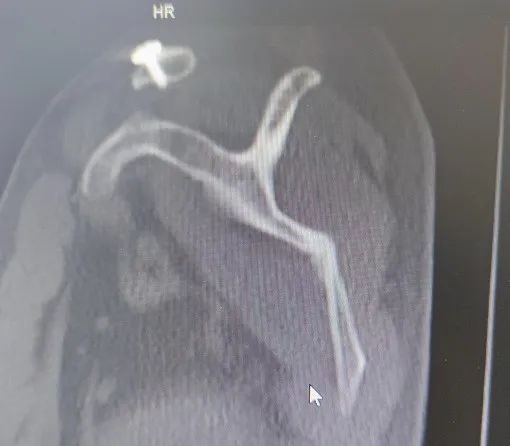

09.07,胸部CT提示“左侧胸膜腔内出现气胸、左侧胸膜腔积液略有增多”,予行胸腔闭式引流术。

手术前